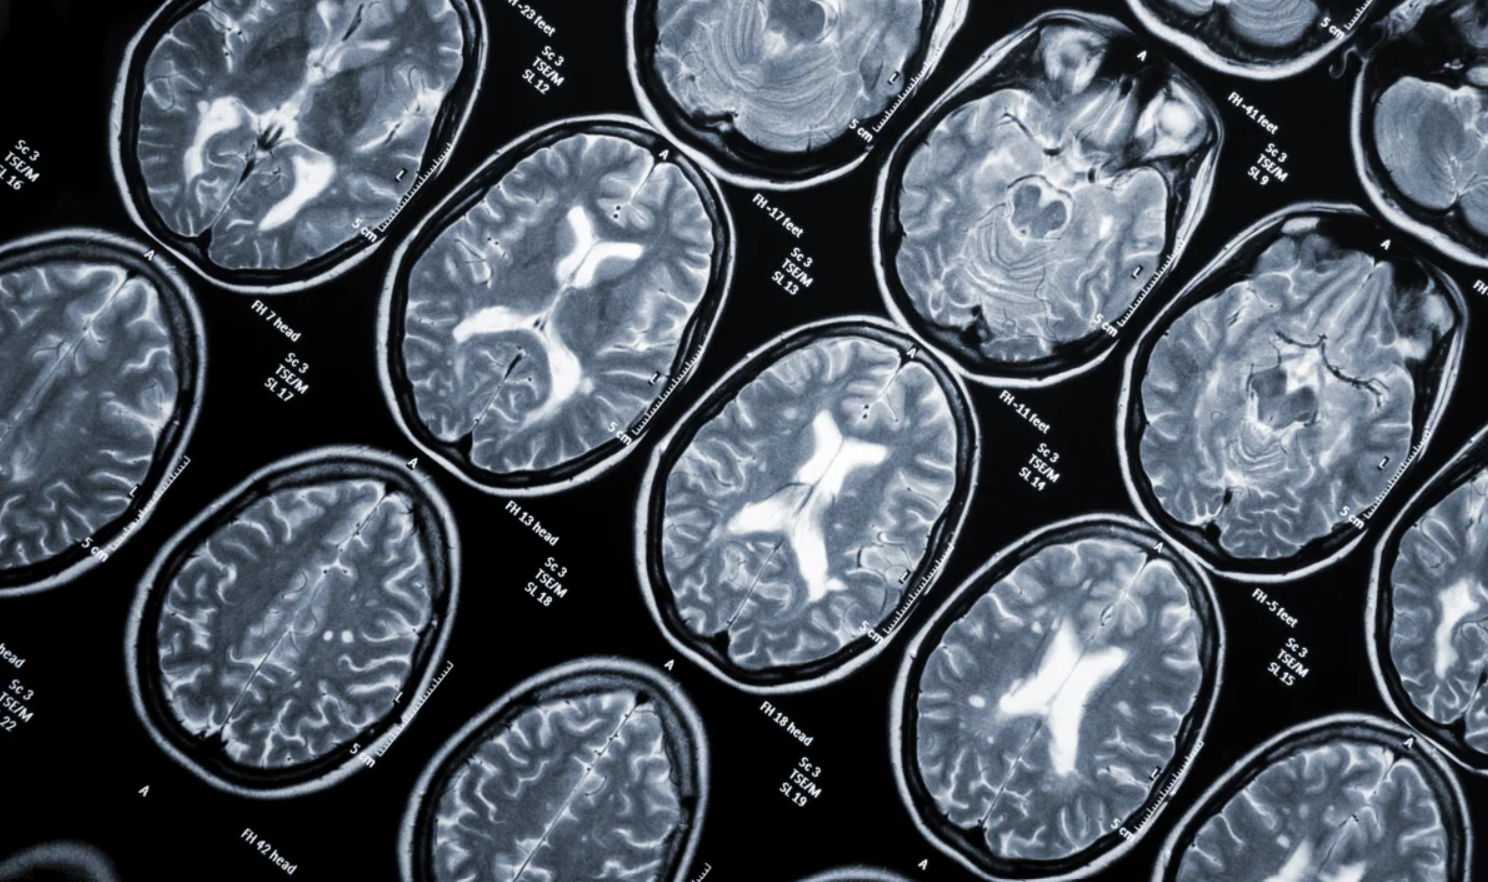

Το ανθρώπινο σώμα διαθέτει πολλές άμυνες για να προστατεύεται από ασθένειες και μολύνσεις. Ωστόσο, σε κάποιες περιπτώσεις, αυτά τα βιολογικά προπύργια μπορεί να στραφούν κατά των υγιών κυττάρων και ιστών, συνήθως κατά λάθος, όπως συμβαίνει με την πολλαπλή σκλήρυνση.